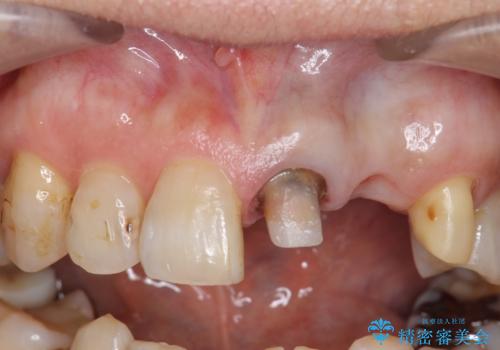

- 左側の前歯の見た目が気になるといらっしゃった方の症例です。

左上1、2番目の歯は仮歯の状態だったので外して状態を確認したところ、左上2は垂直的な歯根破折を認めたため抜歯となりました。左上1は再根管治療を行いました。